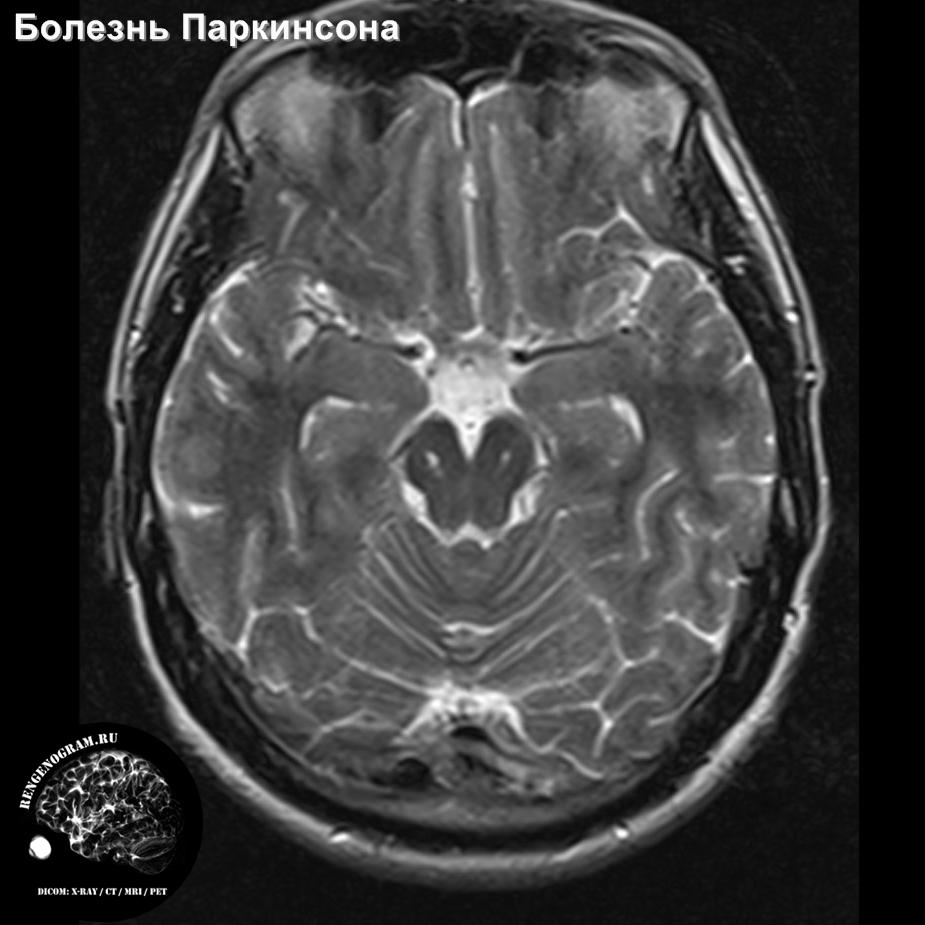

МРТ головного мозга: показания и результаты

Раздел: Визуальный дайджест